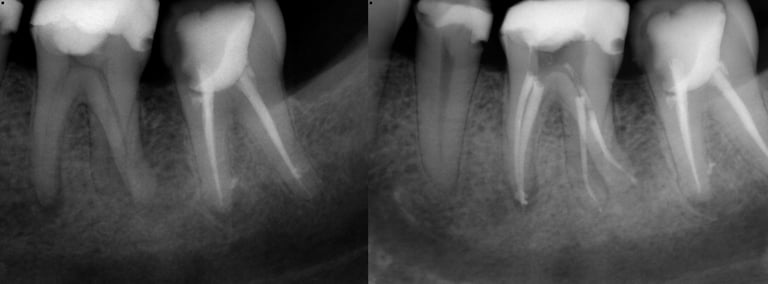

Gallery 2: Retreatment Cases

Retreatment Root Canal Cases with preoperative and postoperative radiographs.

#10 ReTx (original RCT poorly done)

#30 ReTx (original RCT had missed canal)

#14 ReTx (original RCT had missed 4th canal)